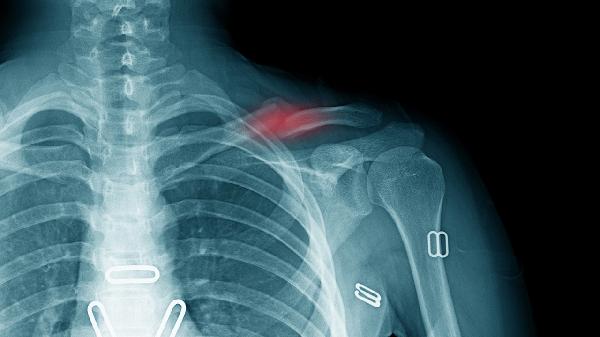

锁骨骨折的手术治疗方法主要有切开复位内固定术、髓内钉固定术、外固定支架固定术、微创钢板内固定术、关节镜下复位固定术。

适用于明显移位或粉碎性骨折。通过手术切口暴露骨折端,使用钢板螺钉系统进行固定。该方法能实现解剖复位,稳定性好,但创伤较大,术后可能遗留疤痕。术后需配合支具保护,定期复查X线观察骨折愈合情况。